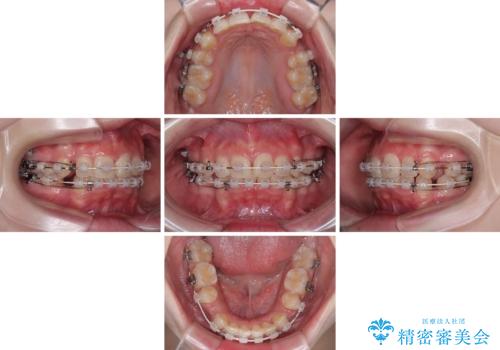

【モニター】デコボコと隠れてしまう前歯 ワイヤー装置による抜歯矯正で美しい口元に

- デコボコになっている前歯を気にして来院された患者様です。

口元の突出感は気になっていないものの、デコボコを解消すると口元が前方に突出する可能性があるため、上下左右の第一小臼歯4本を抜歯して、ワイヤー装置にて矯正治療を行うこととしました。

下の前歯が隠れてしまうほど深く咬みこんでいたため、上顎前歯が前方に突出しているような印象がありましたが、咬み合わせが改善され、整った口元に仕上げることができました。